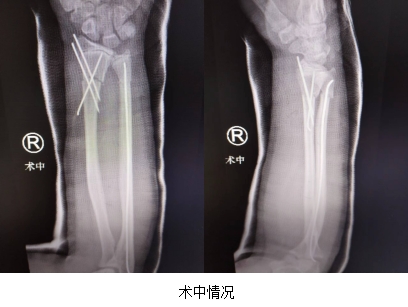

然而,手术并不一定是最佳选择。许多患者家属更愿意选择保守治疗或微创治疗。为了满足这一需求,我们采用了微创小切口治疗的方法。这种方法伤口小、恢复效果好,并且能极大地减少手术创伤。术后,我们会使用管型石膏进行外固定,有助于患者的快速恢复。

这种治疗方法有许多优点。首先,术后伤口小,患者疼痛轻,这大大减轻了孩子的痛苦。其次,恢复时间短,住院时间短,家长可以更快地让孩子回到正常的生活中。即使在严重的情况下,需要切开钢板进行固定治疗,我们也选择美容缝合的方法,以减少伤口愈合时的瘢痕增生,让孩子在恢复后能拥有更美观的皮肤。